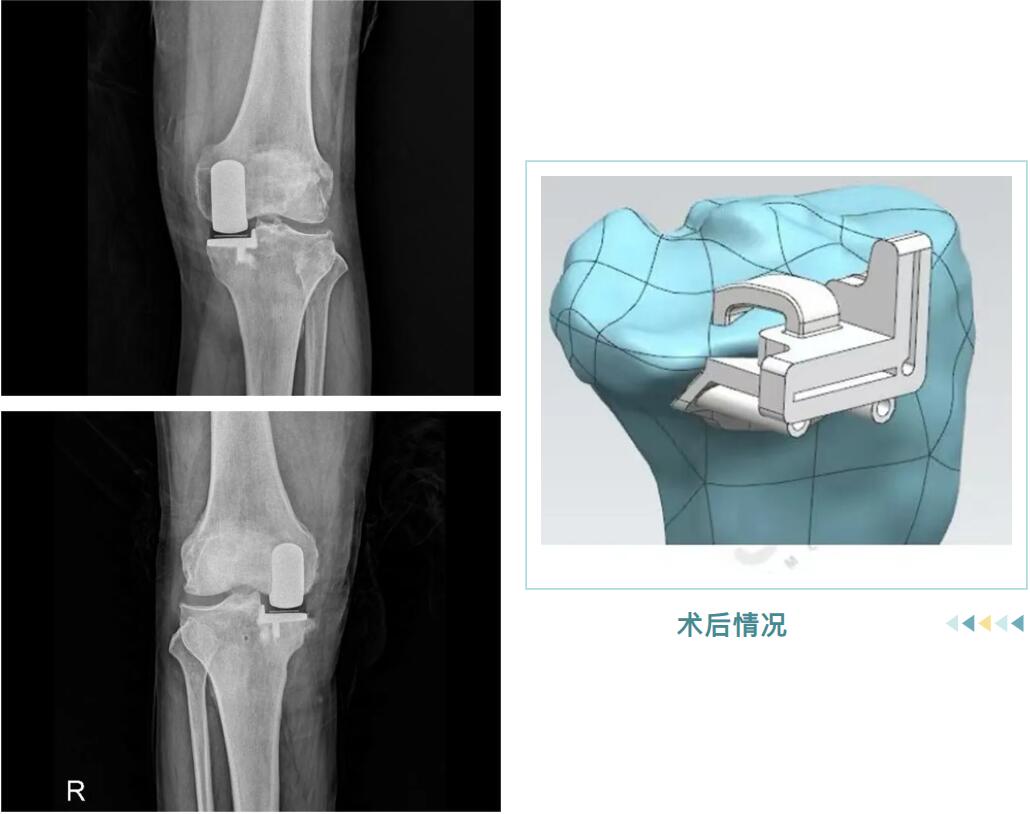

从精准的3D术前规划,到罗院长团队娴熟的手术操作,再到术后个性化的康复指导,整个过程高效而顺利。很快,邵阿伯的“罗圈腿”变直了,术后他轻松站起,行走时仿佛时光倒流十年。

术后情况